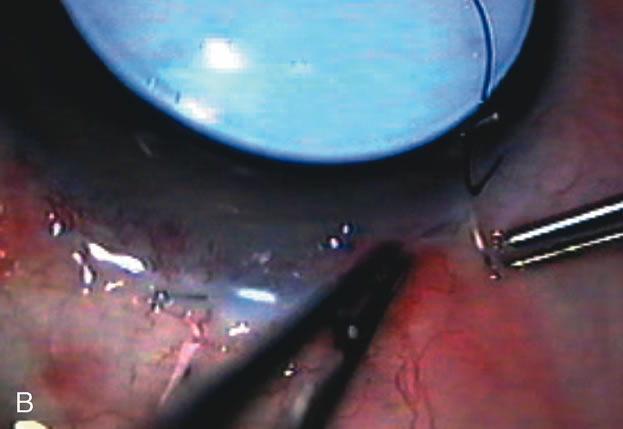

PHACOVISCOCANALOSTOMY AND PHACO/DEEP SCLERECTOMY FOR UNCONTROLLED GLAUCOMA AND SYMPTOMATIC CATARACT

Nonpenetrating procedures as they exist today generally decrease postoperative complications but do not reduce IOP as successfully as trabeculectomy.140 The success rate also appears to be highly dependent on race, length of topical antiglaucoma therapy, and prior ocular surgery.141,142 Deep sclerectomy combined with phacoemulsification results in an IOP reduction similar to phacotrabeculectomy at one year with comparable visual outcome.143 Phacoviscocanalostomy lowers IOP by approximately 33%144 through either a one- or two-site approach145 (Fig. 4). Nonpenetrating procedures are in evolution, and their place in long-term glaucoma care is still unclear.

Fig. 4. Viscocanalostomy with deep sclerectomy and phacoemulsification. Nonpenetrating filtration procedures (NPFS) may be combined with phacoemulsification. Patients with mild disc damage and a history of limited topical drug therapy are the best candidates. Patients who require an IOP in the low teens are not good candidates for NPFS. By definition, NPFS is designed to lower IOP without penetrating into the anterior chamber, thereby avoiding the complications associated with trabeculectomy. Viscocanalostomy is intended to allow aqueous to percolate through a trabeculodescemetic membrane into a subscleral cavern created by the deep sclerectomy. The aqueous diffuses from the cavern into the dilated ostia of Schlemm's canal and into the episcleral venous plexus. A. Fashion a uniform 300-micron superficial scleral flap 1 mm into clear cornea. B. Construct a second 600-micron deep flap that facilitates the unroofing of Schlemm's canal, seen as the darker area. C. Use viscoelastic to dilate the ostia of Schlemm's canal. The major problem with viscocanalostomy is the eventual closure of the ostium decreasing flow to the episcleral plexus. D. Dissect the deep flap anteriorly into clear cornea creating the trabeculodescemetic membrane. This membrane is clearly seen between the scleral spur and the bend of the deep flap. The integrity of this membrane ensures the nonpenetrating portion of the surgery. Another problem with NPFS is the eventual fibrosis of this initially transparent membrane requiring goniopuncture. E. Deep sclerectomy gets its name from removal of the deep flap. Removal of this flap creates the potential subscleral space for accumulation of aqueous before it enters Schlemm's canal and exits the episcleral venous plexus. After removal of the deep flap, the superficial flap is sutured into place and conjunctiva closed. Approximately half of these procedures develop a shallow bleb.